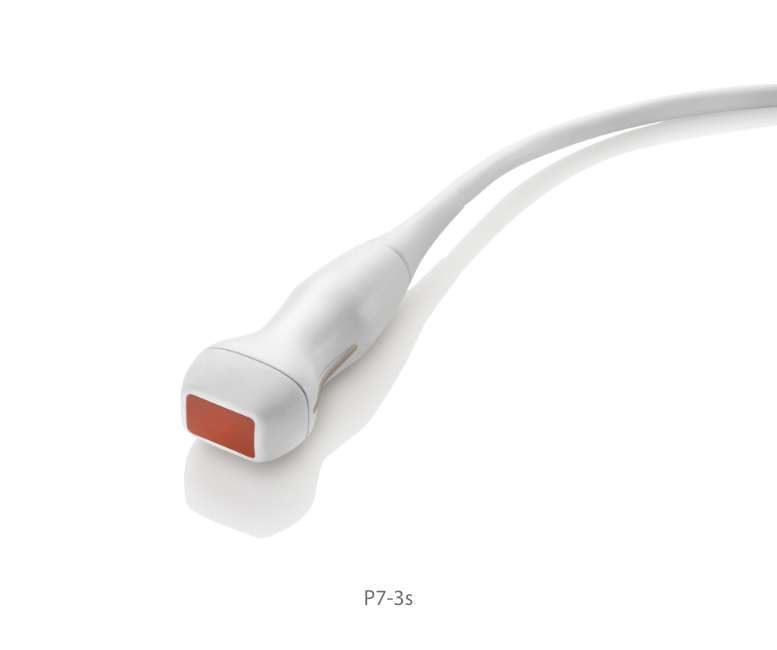

Transducers